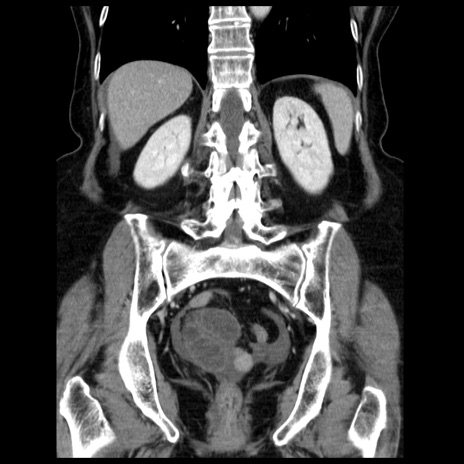

症例13(冠状断像)

【症例】70歳代女性

【主訴】腹痛、嘔吐

【現病歴】15時間程前(昨晩)より腹痛あり。今朝になっても症状の改善なく、嘔吐あり。腹痛も増悪あり、救急外来受診。

【既往歴】子宮癌全摘術後

【身体所見】意識清明、BP 121/72mmHg、P 74bpm、SpO2 100%(RA)、腹部:平坦・軟、腸雑音ほぼ聴取せず。下腹部・心窩部・臍左上に圧痛あり。反跳痛なし。

【データ】WBC 10600、CRP 0.15